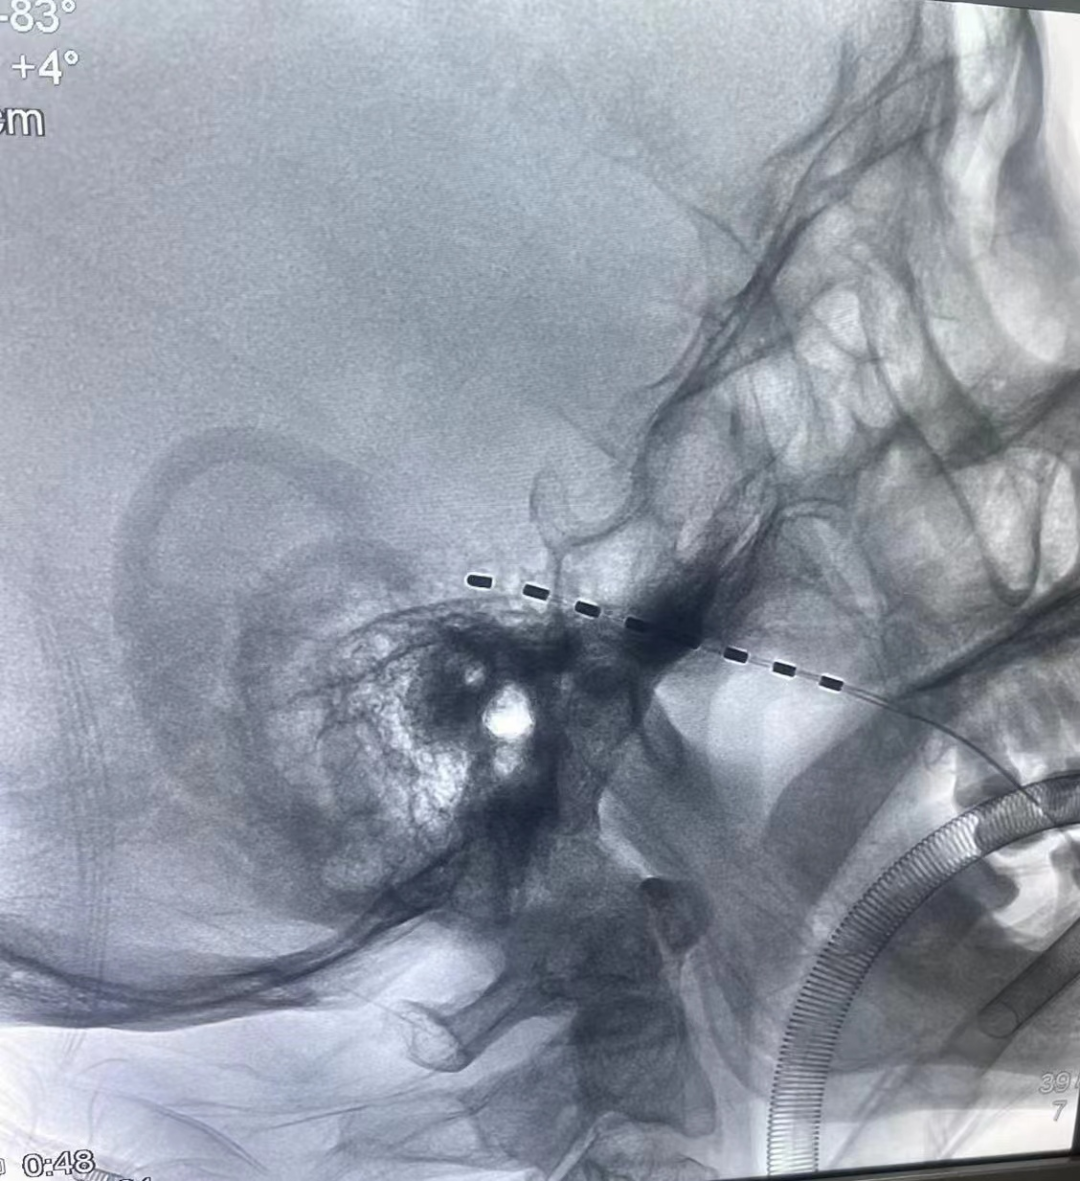

近日,漯河市中心医院疼痛科成功实施院内首例三叉神经半月节电刺激植入术,在DSA精准透视下,可见电极置入位置准确,在刺激器的持续治疗下,患者颜面部疼痛得到控制。

患者为一男性老年,带状疱疹病毒侵犯三叉神经第一支,表现为额面部及眼眶区域刀割样疼痛,疼痛NRS评分:9分。于外院治疗一个多月疼痛控制欠佳,后急诊转入我科,行抗神经病理性疼痛药物应用及超声引导下三叉神经阻滞等治疗,疼痛控制不佳,经过全科医师详细讨论后,决定给予患者行三叉神经半月节电刺激植入术,术后1周,取出刺激器电极,重新行疼痛评估,NRS评分:3分(理想评分)。

该手术是将电极植入到三叉神经半月节,以电流刺激三叉神经,通过干扰疼痛信号向大脑传递,达到治疗疼痛的目的。治疗过程中,根据患者疼痛的具体情况,调整刺激脉冲发生器的参数,接受1周左右的电流刺激,疼痛控制理想后将置入的刺激器取出。